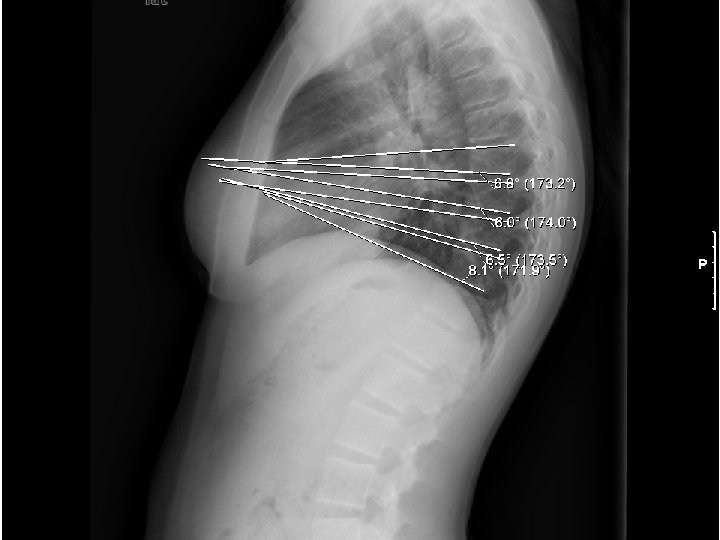

Measure spinal curvature using Cobb method: - Choose the most tilted verterbrae above & below apex of the curve. - Angle b/t intersecting lines drawn perpendicular to the top of the superior vertebrae and bottom of the inferior vertebrae is the Cobb angle.

Measure spinal curvature using Cobb method: